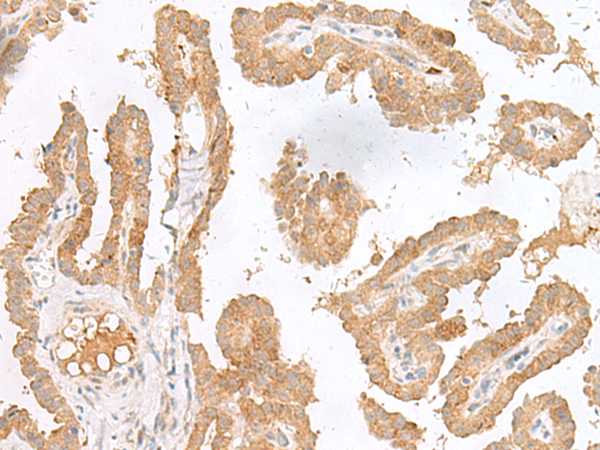

分类: 科研抗体货号: P13443别名:应用: WB,IHC反应种属: Human

分类: 科研抗体货号: P13460别名: LGP1; D11LGP1应用: IHC反应种属: Human

分类: 科研抗体货号: P13458别名: SCN2; GFI-1; GFI1A; ZNF163应用: IHC反应种属: Human, Mouse, Rat

分类: 科研抗体货号: P13457别名: TAMALIN应用: IHC反应种属: Human, Mouse, Rat

分类: 科研抗体货号: P13478别名: GPCR; PGR7; GALR4; GALRL; GPCR-2037应用: IHC反应种属: Human

分类: 科研抗体货号: P13456别名: p97; HC56; HCAP1; HHRF-1应用: IHC反应种属: Human

分类: 科研抗体货号: P13477别名: P138; GIMPC; GOLPH4; GPP130应用: IHC反应种属: Human, Mouse, Rat

分类: 科研抗体货号: P13455别名: DER7; GCS1; CDG2B; CWH41应用: IHC反应种属: Human

分类: 科研抗体货号: P13476别名: GLP; GOLGA6应用: IHC反应种属: Human

分类: 科研抗体货号: P13454别名: GCP2; CKA-3; GCP-2; SCYB6应用: IHC反应种属: Human